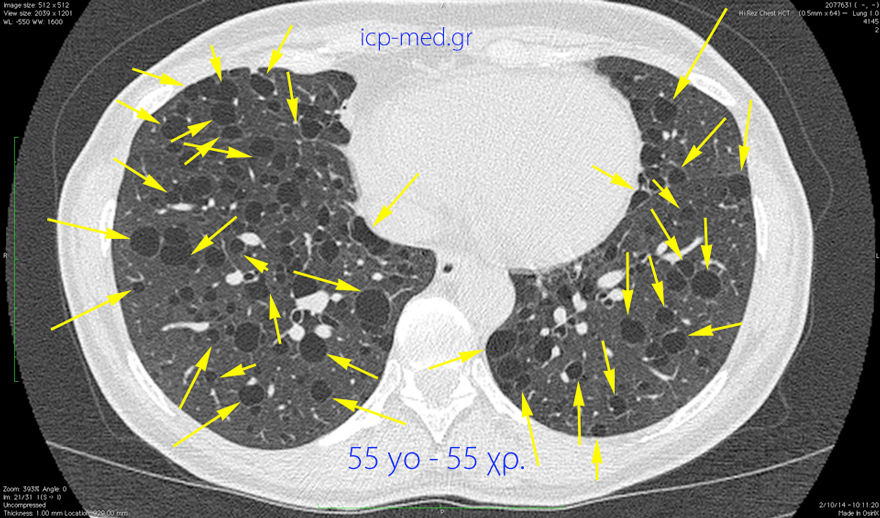

LAM: Lymphangioleiomyomatosis (Lymphangiomyomatosis)

6. CT: numerous Large bullae in a 55-yo post-menopausal♀